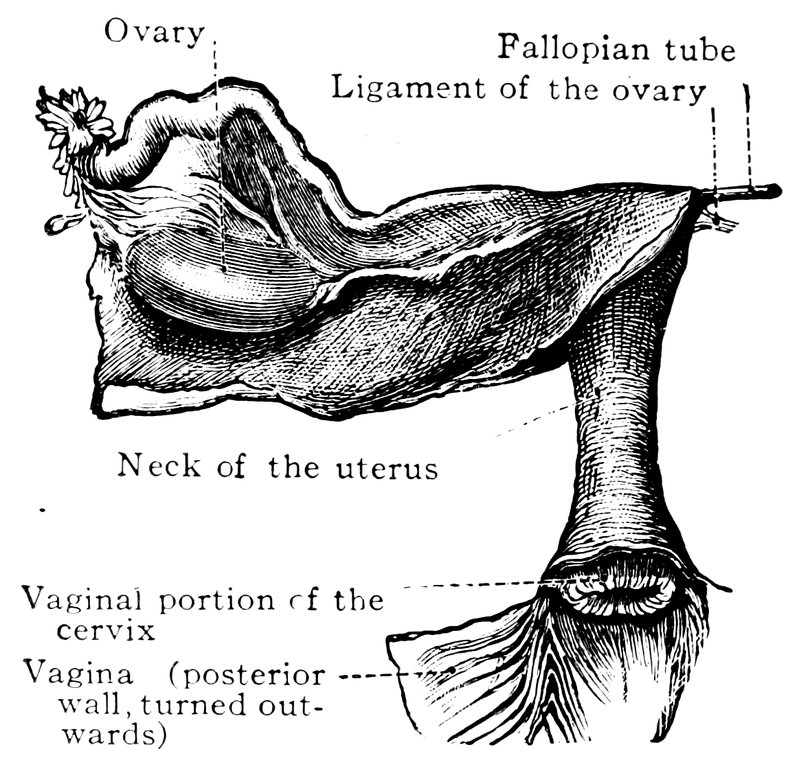

| 2. | Portion of the pelvic viscera in the female, etc. | 9 |

| 50. | The uterus, the left Fallopian tube and the left ovary, etc | 207 |

| 51. | Female internal genital organs in the fully developed state | 208 |